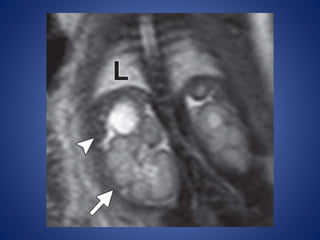

Imaging Features.—At US, Leydig cell

tumors are usually homogeneous and

hypoechoic but less commonly appear

echogenic

At Doppler evaluation, Leydig cell tumors typically have prominent

circumferential blood flow with a lack of internal vascularity.

At MR imaging

- isointense on T1-weighted images and

- hypointense on T2-weighted images compared with

surrounding testicle.

- capsular high signal intensity on T2-weighted images

- show marked homogeneous enhancement